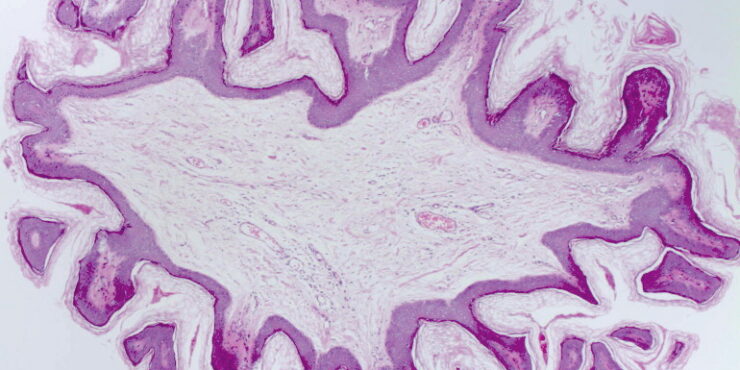

Section of thick skin = مقطع في جلد سميك